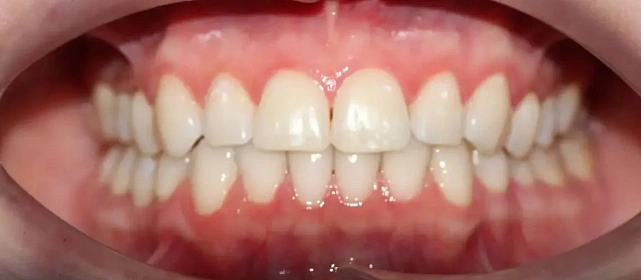

Зубы выровнены, смыкание нормализовано. Установлены несъёмные ретейнеры на обе челюсти, сняты сканы для ретенционных кап.

Решение: Поставили прозрачные элайнеры Click — начали с компактного набора из 20 кап. Основной комплект сделал основной объем работы, но для финальной доводки понадобился дополнительный набор из 10 кап. Итого 30 кап за 23 месяца. Результат — зубы на месте, смыкание в норме. Зафиксировали ретейнеры на обе челюсти, сняли сканы для ретенционных кап.

Мне поставили всего 20 кап, и я думала — за полтора года управлюсь. Вышло чуть дольше, потому что потребовался дозаказ. Но 10 дополнительных кап — это мелочь по сравнению с основным лечением. Зато результат довели до конца, а не остановились на «почти ровно».

Небольшой по объёму случай — 20 кап в основном наборе. Этого хватило для основного выравнивания, но финальная коррекция смыкания потребовала ещё 10 кап. Предпочитаю доработать, чем оставить компромиссный результат. 30 кап за 23 месяца — спокойный темп, без спешки.